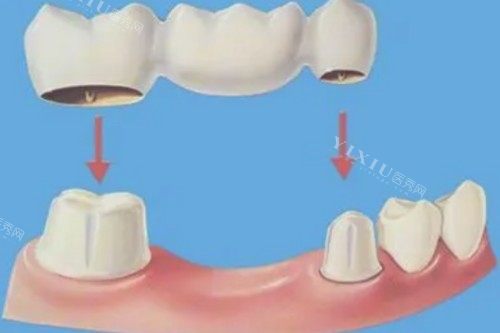

那天我一到桓博口腔,就感觉环境挺不错的。前台的小姑娘热情得很,问清楚我的来意后,很快就给我安排了医生。接待我的是一位经验充足的医生,他先是耐心地询问了我的牙齿情况和平时的一些习惯,接着就给我做了超全的口腔检查。检查过程中,医生一边操作一边给我解释我的口腔状况,还告诉我镶牙的几种方式以及各自的优缺点,就像拉家常一样,让我心里一下子就有底了。

在选择镶牙材料的时候,医生没有像有些地方那样一个劲儿地推荐贵的,而是根据我的实际情况,给我推荐了性价比比较高的材料。他说镶牙不是越贵就越好,适合自己的才是更重要的。我听着觉得挺在理,就按照他的建议选了材料。

确定好方案后,就开始镶牙了。整个过程中,医生和护士配合得相当默契。医生的手法很娴熟,动作也很轻柔,一点都没有让我感觉到特别疼。遇到可能会有点不舒服的步骤,护士还会握着我的手安慰我,让我放松。说实话,我原本心里还挺紧张的,但在他们的安抚下,我慢慢就不那么害怕了。